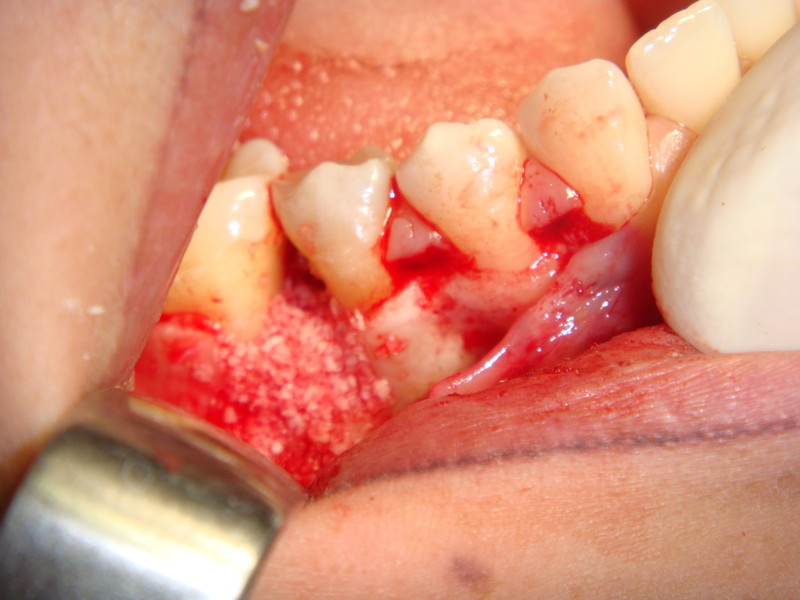

Impianti post-estrattivi complessi con innesto osseo

Impianti Post-estrattivi con innesto di osso e tessuto epitelio-connettivale

Rigenerazione Gravi difetti parodontali

rigenerazione grave difetto parodontale a carico del 46

rigenerazione grave difetto parodontale a carico una intera emiarcata